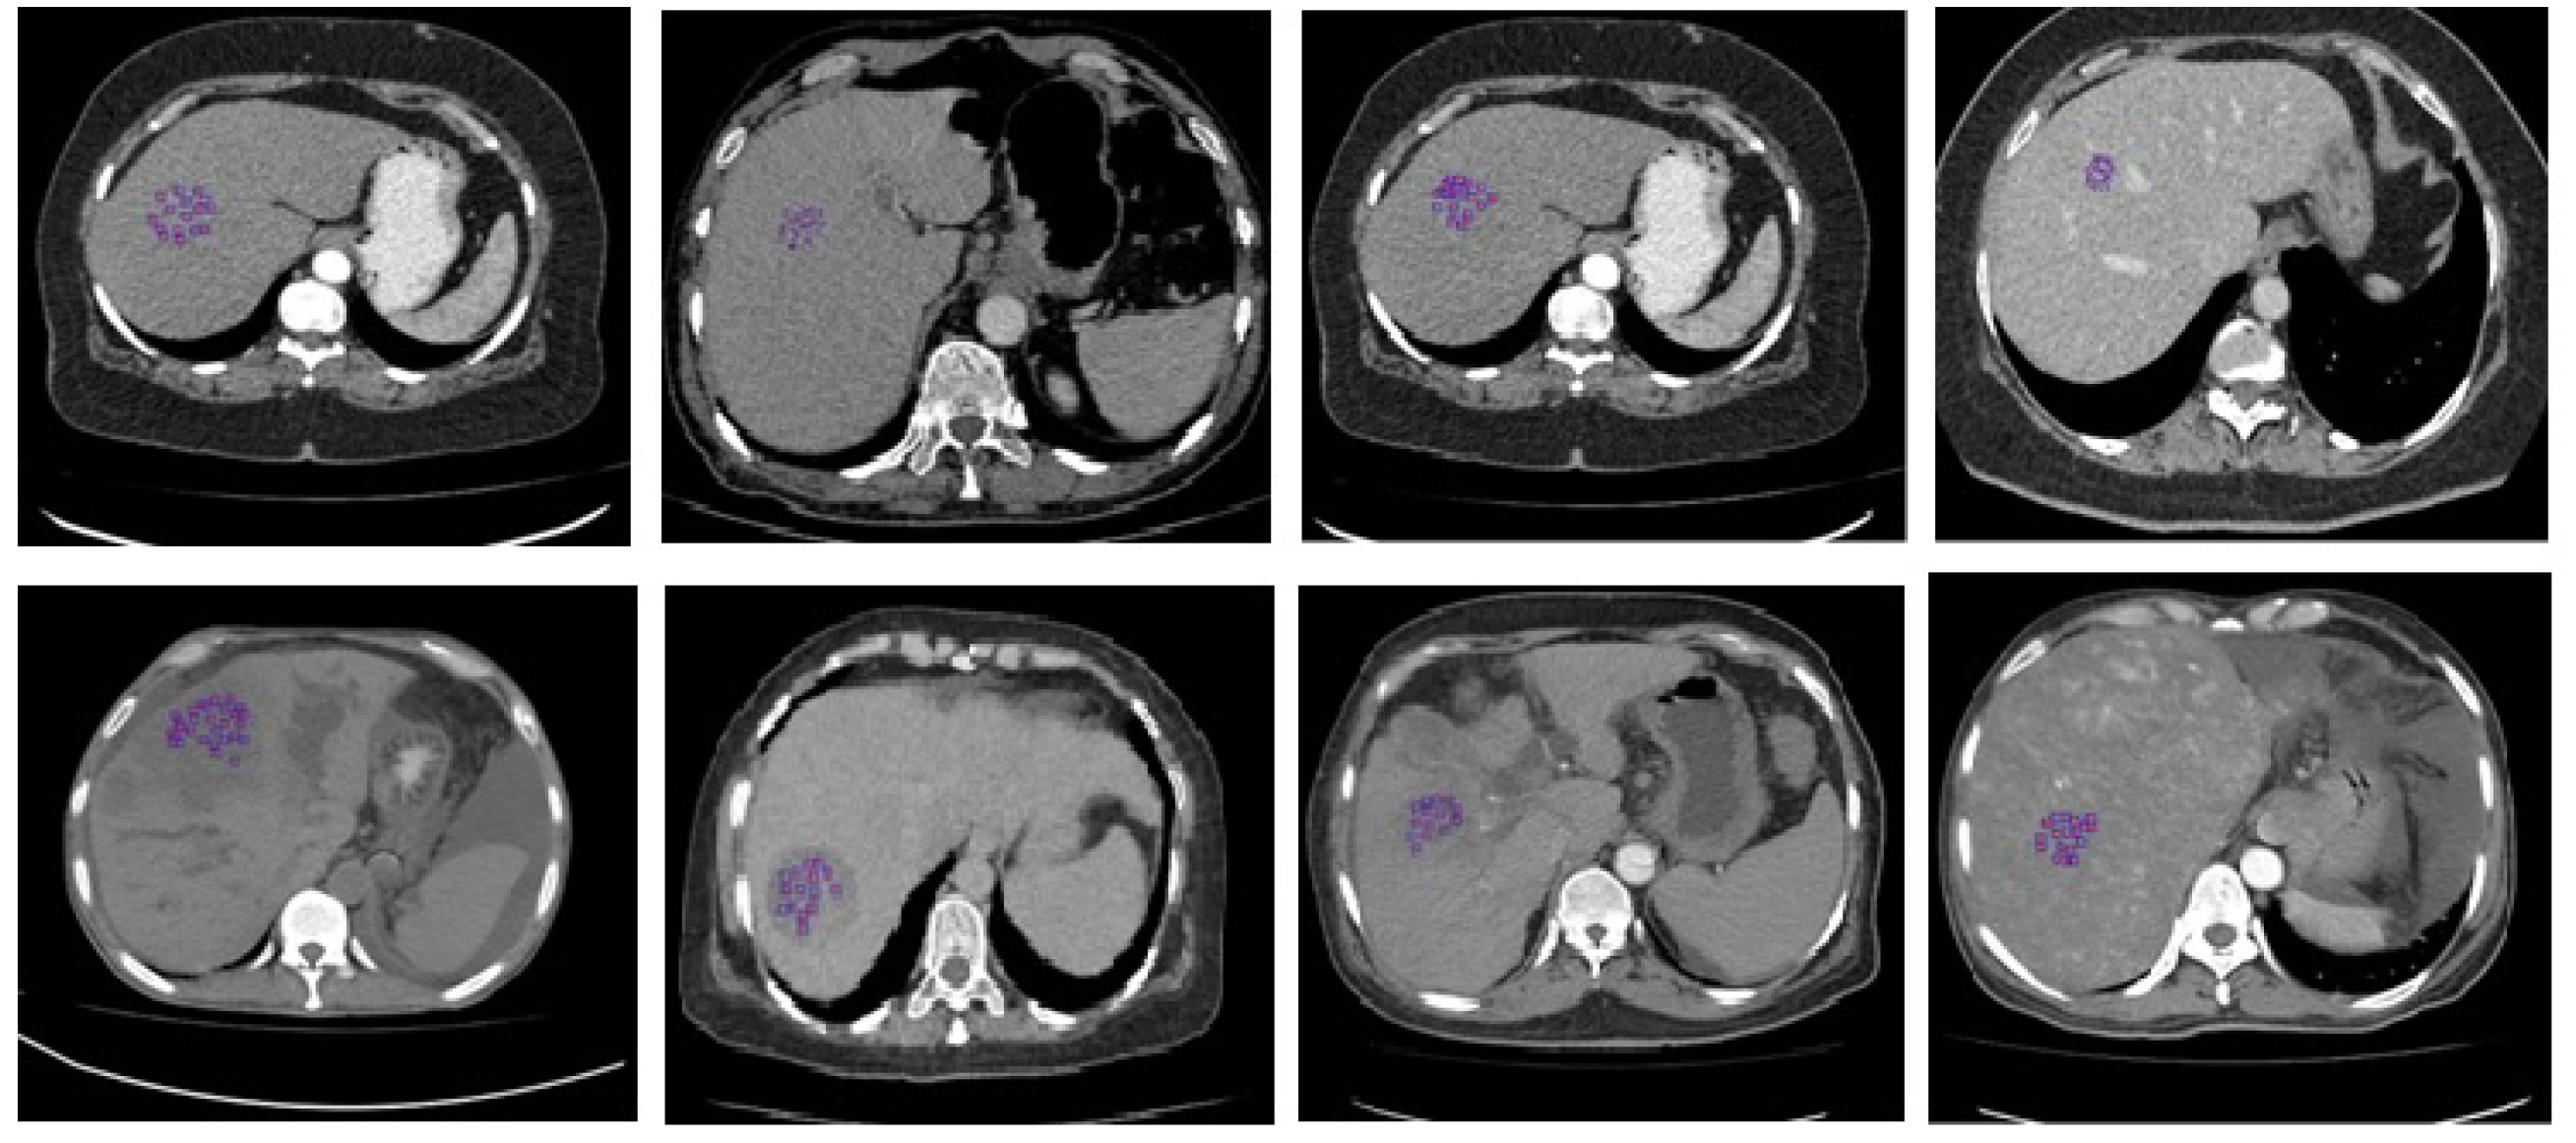

Figure 1.

Some sample images were taken from the proposed database. In the images, abnormalities are highlighted in different subjects’ livers. Row one shows an infected liver or liver abscess and a metastatic liver, whereas row two shows tumor necrosis and an abnormal vascular area in the liver.